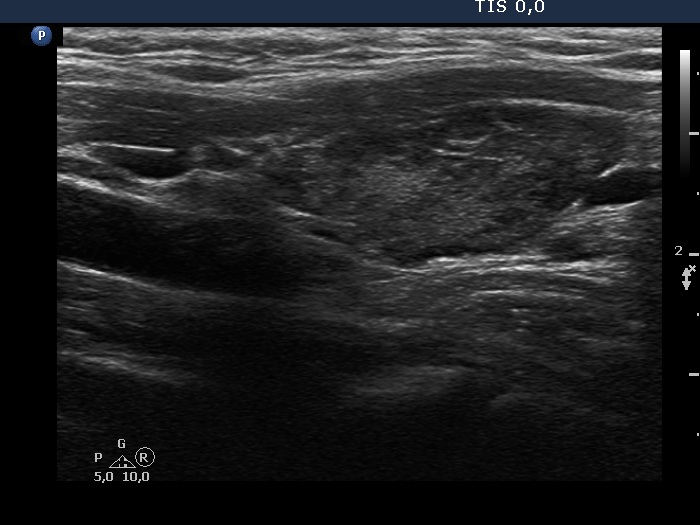

Ultrasound. The thyroid has echonormal and hypoechoic areas. The echogenicity index was greater than 50%. There was a relatively larger echonormal areas in the central-dorsal part of the left lobe. This was less influenced by the underlying thyroiditis. Nevertheless, neither this nor other areas in the thyroid corresponded to true nodules. the so-called honeycombing pattern, i.e., there were numerous small hypoechogenic areas within an echonormal background. The largest hypoechogenic area was misinterpreted as a nodule on previous ultrasound examination. This field was simply the largest of the similarly hypoechogenic parts of the thyroid. Considering the body mass, the thyroid was not enlarged.

It is worth analyzing the presentation of the left lobe. The pattern demonstrates how the thyroiditis infiltrates the normal parenchyma. In this case, the interpretation of echonormal areas should not be a major concern, these are not true nodules.